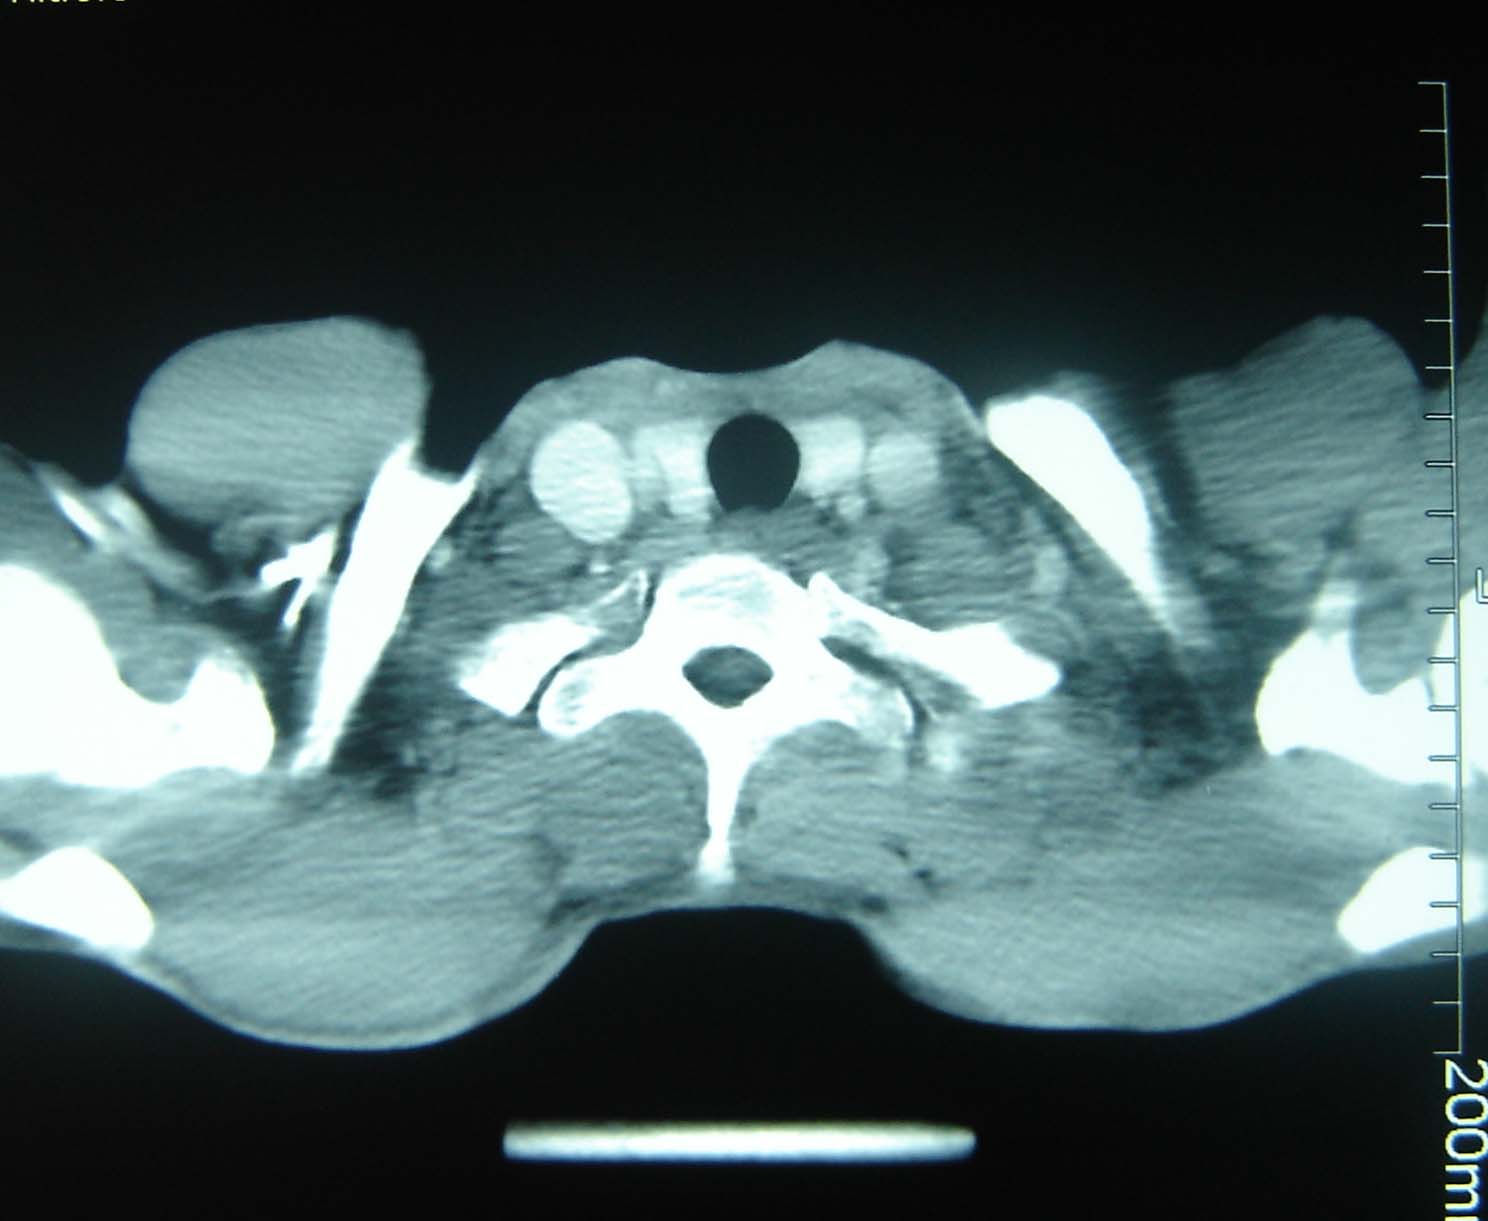

标题: CT25321:两肺多发结节 请会诊 [打印本页]

标题: CT25321:两肺多发结节 请会诊

男 、43岁,咳嗽胸痛,装修工,平时接触粉尘较多,有吸烟史10多年,纤维支气管镜检查未发现异常,胃镜、腹部b超检查亦未发现异常,颈部淋巴结活检未发现肿瘤细胞。

结节病?转移瘤?

1)考虑双肺及胸膜多发性转移瘤。2)肺气肿。